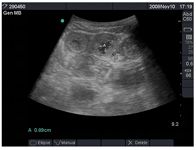

Affected young horses are usually not recognized until they have been infected for one or more weeks. Although they may have mild diarrhea, this is not a consistent finding and the most common presenting complaints are weight loss with a dull attitude (ill thrift). Characteristic findings include marked hypoproteinemia (<3.0 g/dL) in combination with thickened small intestinal walls (wall thickness often >10 mm; normal is <3 mm) detected on abdominal ultrasonography (Figure 2). In addition, more careful palpation of the ventrum often reveals mild to moderate ventral edema. In fact, these findings are nearly pathognomonic for EPE in a weanling or yearling.

Figure 2. Transabdominal ultrasonographic image of a weanling foal with severe hypoproteinemia and thickened small intestinal walls consistent with Lawsonia intracellularis infection